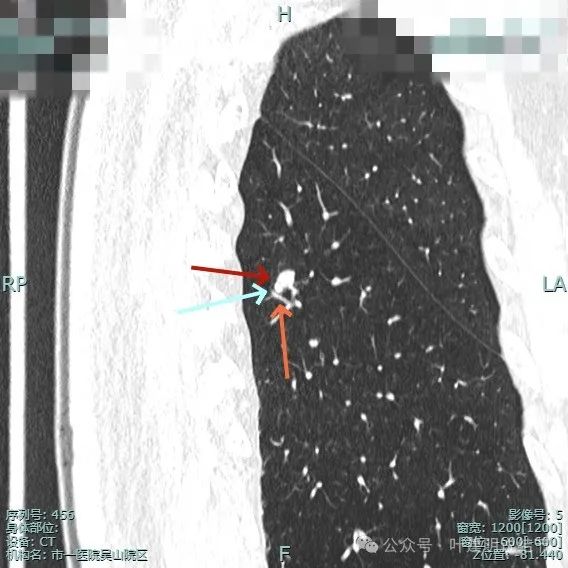

邻近血管与之近但两者间有间隙,说明非普通伴水肿的炎性病灶;病灶膨胀感显得较明显,有鼓鼓的感觉。

进入的血管壁显得毛糙,有异常增粗,结节与邻近血管之间有间隙征,整体有膨胀感。

像个腰子的形态,靠下侧深凹进去,说明有收缩力吗?还是月牙铲征?